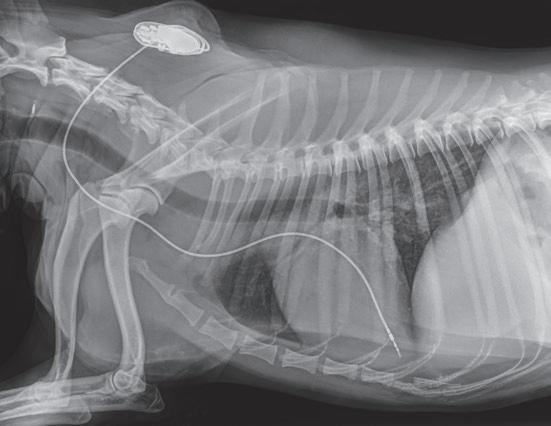

La radiología intervencionista es una especialidad que se encarga del diagnóstico y tratamiento de una gran cantidad de patologías de una forma mínimamente invasiva. Para realizar estos procedimientos es imprescindible disponer del equipamiento adecuado, tener nociones tanto de la instrumentalización como de las diferentes técnicas, y conocer con precisión la anatomía del paciente. Se trata de técnicas cada vez más implementadas en la clínica diaria ya que permiten solucionar diferentes patologías con una menor agresión a nivel tisular, una rápida recuperación, son procedimientos sin dolor, rápidos y seguros, suponen un menor coste respecto a otras cirugías invasivas, y constituyen una alternativa terapéutica a pacientes que no se pueden operar de forma convencional. Entre las más frecuentes destaca el cierre del conducto arterioso persistente, valvuloplastias en estenosis pulmonar, oclusión de shunts portosistémicos, implantación de marcapasos y colocación de stents

Para realizar la mayoría de los procedimientos quirúrgicos, es imprescindible disponer de un equipo de fluoroscopia, que permite la adquisición rápida de

imágenes basadas en rayos X y posteriormente las convierte en una señal de vídeo en tiempo real. Estas imágenes pueden manipularse ofreciendo funciones como la angiografía de sustracción digital, mapeo vascular y ampliación. Respecto a una radiografía, la exposición de rayos X necesaria para realizar una fluoroscopia es baja, pero debido a la duración de las series de imágenes que habitualmente se toman, el nivel de exposición en los pacientes suele ser elevado. Por lo tanto, es importante controlar el tiempo de exposición y llevar un registro de este. El fluoroscopio debe estar situado en una sala adecuada para su uso seguro, y todo el personal que entre en la sala de fluoroscopia debe protegerse de la radiación utilizando un delantal plomado, protectores de tiroides y gafas plomadas.